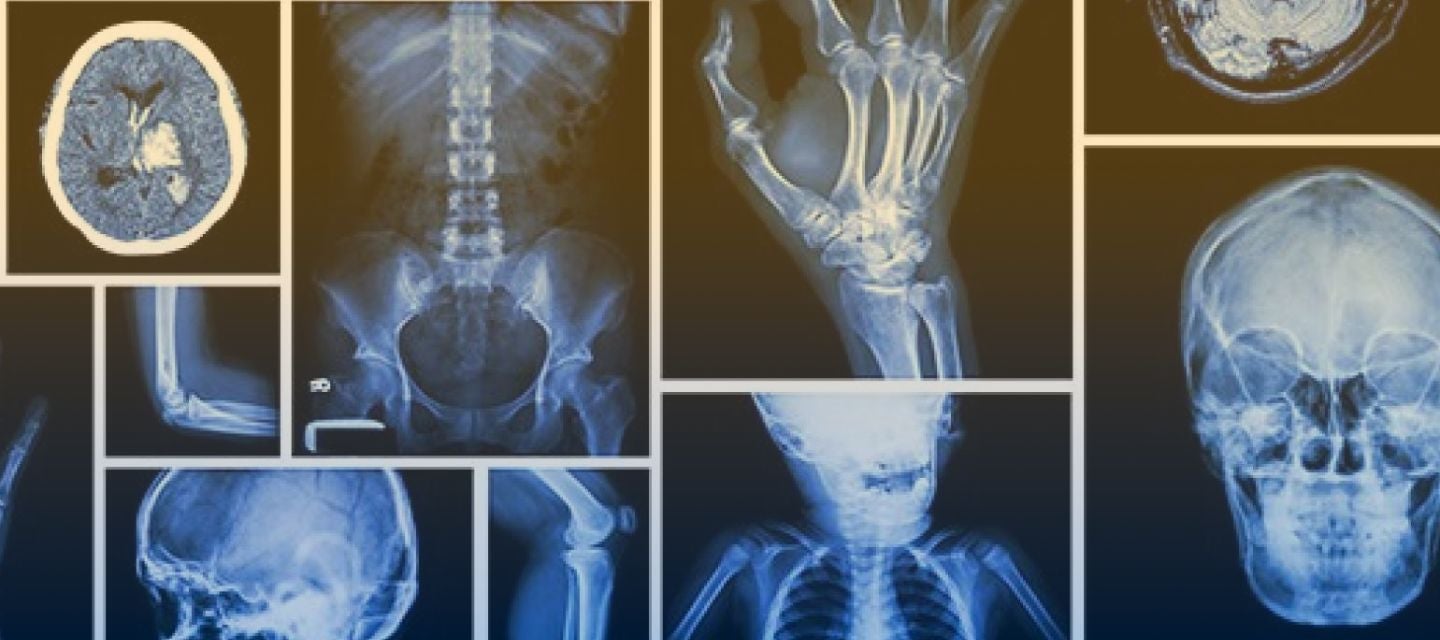

Across Australia our clinics work closely with physiotherapists, offering a full range of musculoskeletal investigations including x-ray, CT and MRI procedures. With imaging and reports available online at I-MED Online, we can help you to quickly establish a diagnosis and ensure the most effective rehabilitation for your patients.

Chiropractors and osteopaths often rely on x-ray and MRI when there is a suspected serious pathological cause of a patient’s pain, or to confirm diagnosis of a patient’s musculoskeletal issues. With imaging and reports available online at I-MED Online, we can help you to quickly confirm a diagnosis and ensure the most effective management for your patients.

X-ray